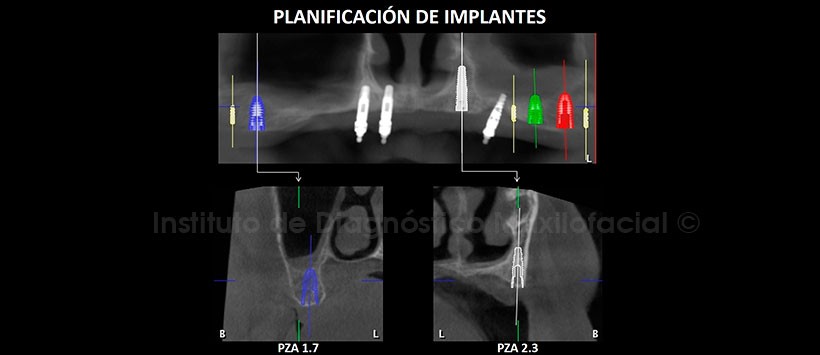

En la tomografía computarizada de haz cónico (TCHC), se realiza la planificación virtual de colocación de cuatro implantes dentales en zonas de piezas 17, 23, 26 y 27 (Figura 2, 3), y sobre la planificación se realiza la confección virtual de la guía quirúrgica (Figura 4). En la reconstrucción 3D (Figuras 5) se aprecia con detalle la orientación y la disposición final de los implantes dentales a ser colocados, además se observa la guía quirúrgica confeccionada virtualmente que posteriormente fue impresa físicamente para su utilización en el procedimiento quirúrgico (Figura 6).